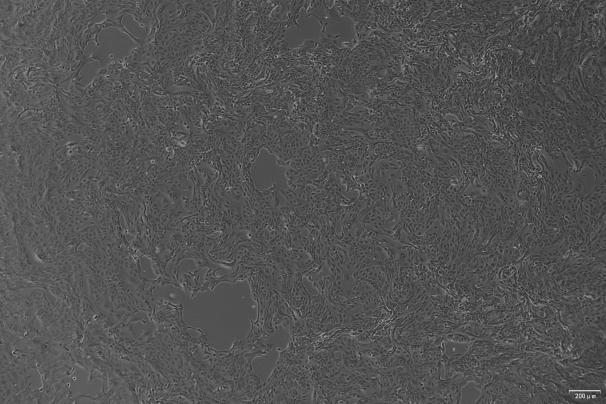

人膀胱癌细胞系(KU-19-19)是 1993 年从一位 76 岁男性患者的膀胱移行细胞癌(3 级,pT3b)中建立的,该细胞呈现典型的上皮样形态,适合贴壁培养,能够分泌数种造血细胞因子和绒毛膜促性腺激素。

贴壁生长;上皮细胞样 |